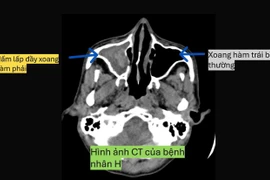

Mới đây, một bệnh nhân viêm xoang biến chứng mù mắt, may mắn được các bác sĩ kịp thời lấy lại thị lực. Thực tế viêm xoang không chỉ gây tổn thương ở mắt mà còn ảnh hưởng cả não và tĩnh mạch...

Nếu bị viêm xoang do nấm mà không điều trị kịp thời có thể gây nhiều biến chứng nặng như phá hủy các thành xoang, xâm lấn hốc mắt, sọ não gây mù lòa, viêm màng não, thậm chí ảnh hưởng đến tính mạng.

Hầu hết bệnh nhân viêm xoang biến chứng mắt mà đã mù thì tỷ lệ điều trị để mắt sáng trở lại bình thường rất hiếm. Đa số bệnh nhân chỉ thấy lờ mờ hoặc bị mù vĩnh viễn.